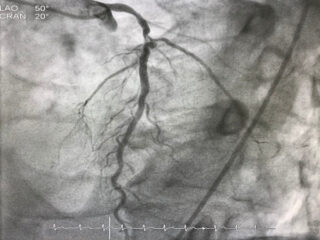

IVUS Guided Multi Vessel CHIP Case With Rotablator Clinical Presentation A 77 years, Male presented with severe angina Findings Patient is with old CVA history presented with Anterior non-ST Elevation

Coronary angiography is a procedure that uses X-rays to visualize and inspect arteries. It shows if there are any blocked arteries and how well your heart muscle is working.

Chip angioplasty or coronary angioplasty, is a procedure that is done to enhance heart health by opening blocked or narrowed arteries. This latest intervention is a step ahead in the treatment of coronary artery disease.

Angioplasty is a surgical intervention in which the occlusive/hypertrophied vessel or coronary artery of the heart is occluded by a balloon. This form of medical therapy is usually provided after myocardial infarction to restore arterialisation and shorten the course of damage. The surgeon puts a stent inside the lumen so that it stays patent in restoring blood flow. This early coronary angioplasty after myocardial infarction (within 3 months) also reduces future myocardial heart disease.